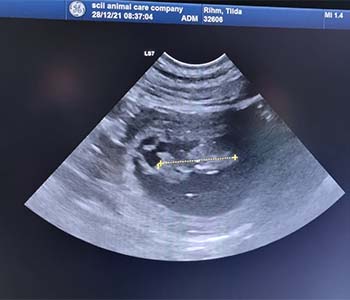

03.01.2022 - "Vom Bauch mitten ins Herz"

Was wir schon seit Tagen vermutet haben, wurde nun endlich wahr. Unsere Tilda hat ihr Geheimnis gelüftet.

Tilda ist trächtig!

Auf dem Ultraschall konnte man eindeutig mehrere kleine Fruchtanlagen erkennen. Sie sind jetzt schon ca. 1,75cm groß.

Wir sind so überglücklich und freuen uns schon sehr. Wir erwarten den Wurf Anfang Februar und hoffen auf gesunde schwarze und braune Welpen aus der Verpaarung *Xiao* Loretta Costa Retrievers Xiao und *Tilda* Almond Eyes of Heidelberg Hills.